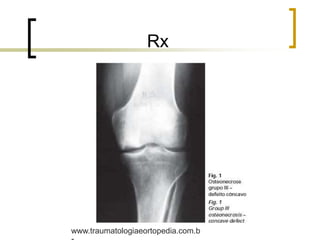

Rx

Classificação - Koshino

 Tipo 1: radiografias normais e cintilografia positiva, se

nenhuma alteração for observada em 6 meses, permanecerá

neste estágio;

 Tipo 2: radiografias com aplanamento do planalto tibial e do

côndilo femoral e cintilografia positiva;

 Tipo 3: radiografias com áreas de radioluscência, halo

esclerótico no foco de ON e áreas de esclerose distal a este –

Sinal do crescente; cintilografia positiva.

Obs 1.: no estágio 3, quando o acometimento atinge até 2,5 cm² é

menor a possibilidade de futura osteoartrose, quando as

lesões são maiores do que 10 cm² o prognóstico para

osteoartrose é quase certo.

Obs 2.:menor que 3,2 cm² são tratadas conservadoramente e

maiores que 5 cm² , cirurgicamente.